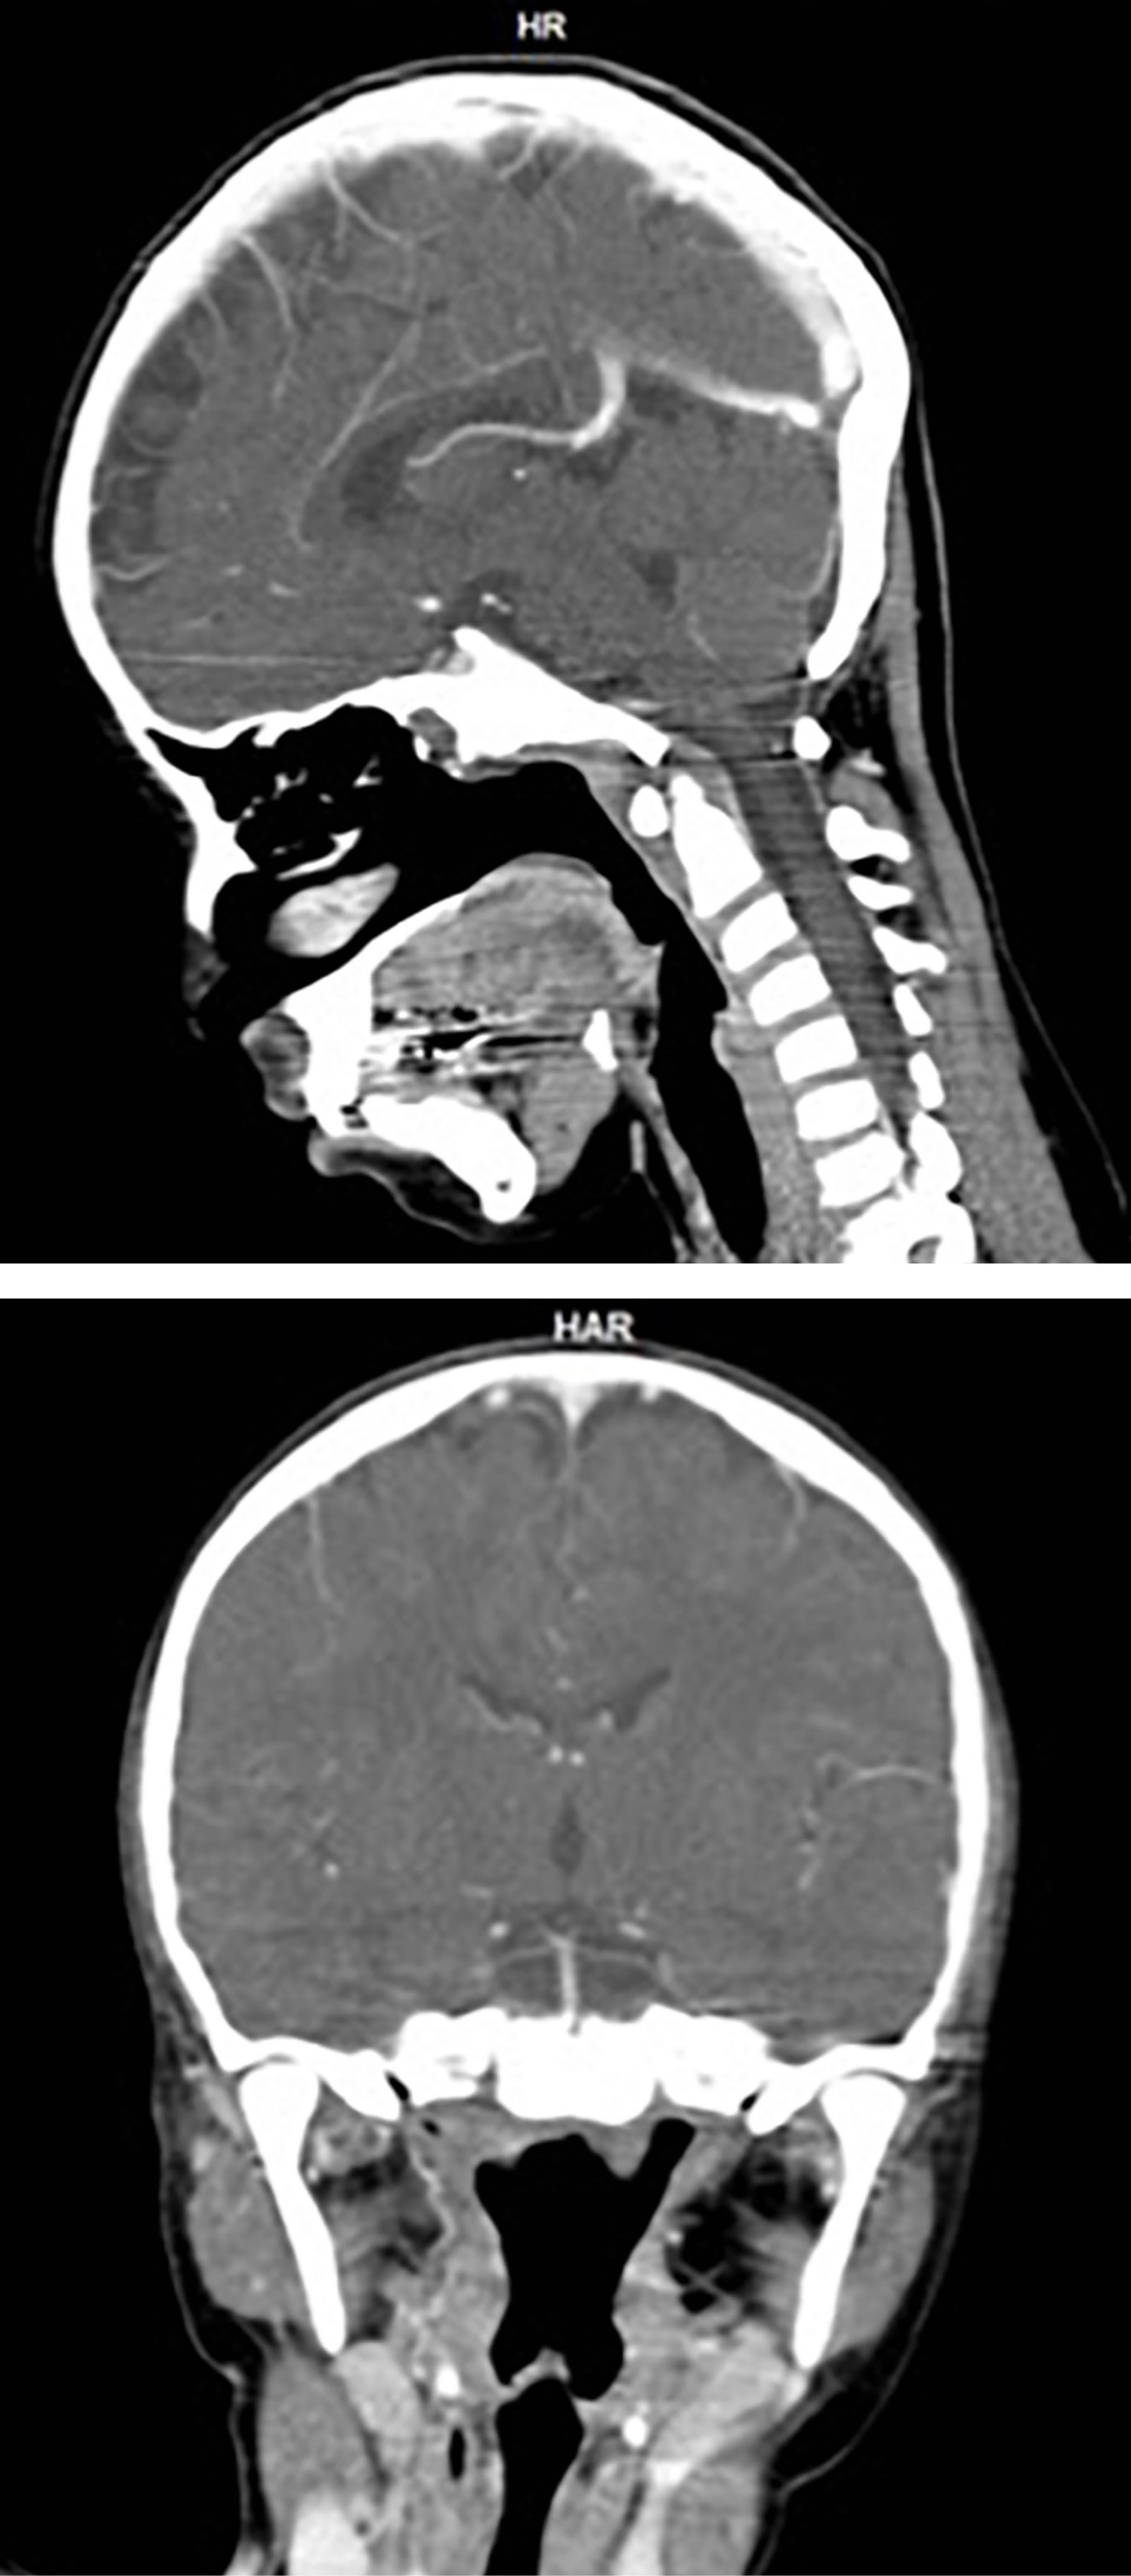

En junio la paciente requiere hospitalización por dificultad para la alimentación, por datos de parálisis facial (imposibilidad para levantar la ceja derecha y cerrar los ojos, así como desviación de comisura labial). En una nueva TAC se observó aumento de volumen cervical bilateral, el cual no fue observado previamente, además de un tumor homogéneo isodenso que obstruye totalmente la nasofaringe, infiltrando tejidos blandos de cuello y paladar blando (Figura 1). Se le realiza traqueostomía y gastrostomía para presentar vía aérea que se encontraba parcialmente obstruida.

Figura 1